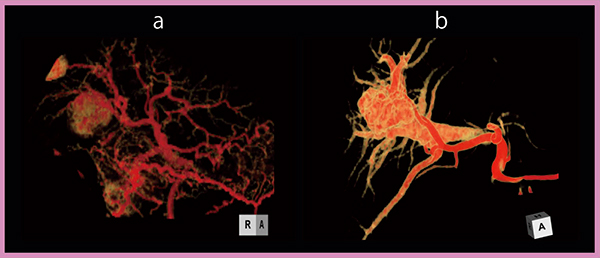

HCCの血行動態の観察において,32mmの撮影範囲を有する64列MDCTに比べ,320列ADCTでは160mm幅を撮影できるという点で臨床的意義は大きい。64列MDCTでは,全肝の血行動態の観察にはearlyとdelayの2相をフュージョンした画像を作成し,HCCに注目する場合にはSingle Slice Dynamic CTHAで撮影した32mmの領域の血流評価をしていた。一方,320列ADCTでは全肝のDynamic Volume Scanが可能で,HCCが複数ある場合にも個々の血行動態の違いをとらえることができる(図3)。

Dynamic Volume Scan でHCCとAPシャント/門脈瘤(血管性病変)の血行動態を比べると,血流やwashoutの様子,肝臓実質の濃染に明らかに違いがあることがわかる(図4)。今後は,血行動態の詳細な検討が必要と考えている。

図4 全肝Dynamic Volume Scan:HCC(a)とAPシャント/門脈瘤(b)の比較